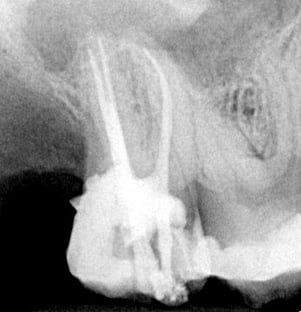

Ist der sogenannte Nerv (richtig: das Zahnmark) schwerwiegend geschädigt, abgestorben oder

infiziert, muss er aus dem Zahn entfernt werden. Die Wurzelkanäle, in denen der Nerv saß, müssen gereinigt, gespült und desinfiziert werden. Abschließend sollten sie bis zur Wurzelspitze mit

einem biologisch verträglichen Material abgefüllt werden.

Diese Behandlung stellt hohe Ansprüche an den Behandler (Lupenbrille oder Mikroskop) und

Instrumente (Biegsamkeit, Bruchfestigkeit). In unserer Praxis in Bremen bieten wir Ihnen Endodontie unter Lupenbrille mit modernsten Instrumenten und thermoplastischer Wurzelfüllung bis in die

Seitenkanäle.